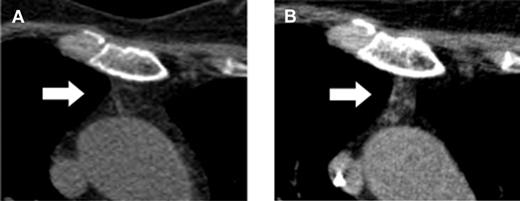

Here, Vago et al have made an unexpected observation and might have found a way to induce a surprisingly rapid de novo generation of naive RTEs with a broad and protective immune repertoire without an increased risk of GVHD.1 They report on 28 adult patients who participated in a multicenter phase 1/2 clinical trial, TK007. In this trial, purified mature donor-derived T cells that were retrovirally transduced with the Herpes Simplex Thymidine Kinase suicide gene (TKpos cells) were serially infused into adult patients with various hematologic malignancies after myeloablative conditioning and transplantation of highly purified CD34+ stem cells from haploidentical donors.8 In case of occurrence of GVHD, the suicide mechanism can be activated by ganciclovir to abrogate GVHD. Twenty-two of the 28 patients who received the purified TKpos cells showed a rapid recovery of T cells that was associated with a concomitant improvement of the clinical outcome and reduction of transplant-related mortality. Patients not receiving TKpos cells failed to attain T-cell immune reconstitution and had a dismal outcome mainly due to infectious complications. Therefore, the infusion of TKpos T cells seemed to induce a rapid and robust T-cell reconstitution. Interestingly, further follow-up of these patients revealed that the regenerating CD3+ T cells failed to express the TK suicide gene (TKneg cells), while donor-derived TKneg cells were not detected in patients who did not receive genetically modified T cells nor in those who failed to engraft TKpos cells. The TKneg cells were enriched in the CD4+ T-cell subset and an increase of the T-cell subset with a naive phenotype (CD62L+CD45RA+) was seen during the observation period even in elderly patients. In addition, measurement of the sjTRECs in patients treated with the TKpos cells demonstrated an increase of sjTREC counts parallel to the increase in the naive T-cell subset. Strinkingly, an increase of the serum levels of IL-7 was observed early after TKpos T-cell add-backs followed by a concomitant rise in peripheral T-cell counts. Further analysis of the reconstituting naive TKneg cells revealed that most of the TKneg naive CD4 cells coexpressed CD31, indicating a continuous output of RTEs, compatible with the computed tomography–based observation of increased thymic tissue even in elderly patients (see figure).

Computed tomography–based increase of the thymic density in a 64-year-old patient before (A) and after (B) add-backs of TKpos T cells. For detailed description see Figure 4 in the article by Vago et al that begins on page 1820.1